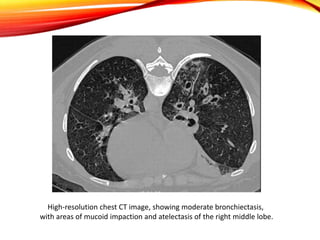

High-resolution chest CT image, showing moderate bronchiectasis,

with areas of mucoid impaction and atelectasis of the right middle lobe.